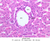

Sections through the wall of the gall bladder appear on slide B-33 (H&E [2.5x, 10x, 20x-labeled, 40x-labeled] [2.5x, 10x, 20x, 40x]). As you examine the epithelium, try to identify the striated border, which functions in absorbing water from the bile. Look for lymphocytes, capillaries and small mucous glands in the lamina propria; lymphocytes often appear to invade the epithelium itself. The gallbladder does not have a discernible submucosa; rather, a muscularis layer, consisting of smooth muscle and connective tissue underlies the mucosa. Some sections may permit identification of both a tunica adventitia, which binds the gallbladder to the liver, and a tunica serosa where the gallbladder faces the peritoneal cavity.

B33, Gallbladder, 2.5x (H&E) B33, Gallbladder, 10x (H&E) B33, Gallbladder, 20x Labeled (H&E) B33, Gallbladder, 40x Labeled (H&E) B33, Gallbladder, 2.5x (H&E) B33, Gallbladder, 10x (H&E) B33, Gallbladder, 20x (H&E) B33, Gallbladder, 40x (H&E)